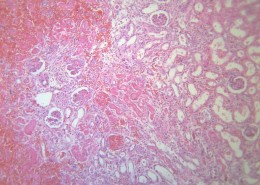

肾小管renal tubule 与肾小囊壁层相连的一条细长上皮性小管,具有重吸收(reabsorption)和排泌作用(secretion).肾小管按不同的形态结构,分布位置和功能分成三部分;近端小管,细段和远端小管。肾小管在肾髓质中。